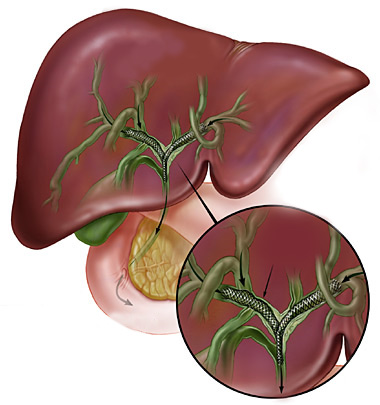

A CPRE é um procedimento que pode ser feito para examinar o fígado, vesícula biliar, vias biliares e o pâncreas. O fígado é um órgão que, entre outras coisas, produz um líquido chamado bile que auxilia a digestão. A vesícula biliar é um órgão pequeno, em forma de pêra, que armazena a bile até que seja necessária para a digestão. Os ductos biliares são canais que transportam a bile do fígado para a vesícula biliar e duodeno. Estes ductos são chamados algumas vezes de árvore ou via biliar. O pâncreas é um órgão que produz substâncias químicas que ajudam a digestão.

O médico verifica a abertura do tubo de drenagem de bile do fígado. Este tubo de drenagem é chamado de ducto biliar comum. Drena bile do fígado e suco pancreático para o duodeno para ajudar na digestão das gorduras. O orifício de saída do ducto biliar no parede do duodeno chama-se papila duodenal.

A CPRE é um procedimento que pode ser feito para examinar o fígado, vesícula biliar, vias biliares e o pâncreas. O fígado é um órgão que, entre outras coisas, produz um líquido chamado bile que auxilia a digestão. A vesícula biliar é um órgão pequeno, em forma de pêra, que armazena a bile até que seja necessária para a digestão. Os ductos biliares são canais que transportam a bile do fígado para a vesícula biliar e duodeno. Estes ductos são chamados algumas vezes de árvore ou via biliar. O pâncreas é um órgão que produz substâncias químicas que ajudam a digestão.

O médico verifica a abertura do tubo de drenagem de bile do fígado. Este tubo de drenagem é chamado de ducto biliar comum. Drena bile do fígado e suco pancreático para o duodeno para ajudar na digestão das gorduras. O orifício de saída do ducto biliar no parede do duodeno chama-se papila duodenal.